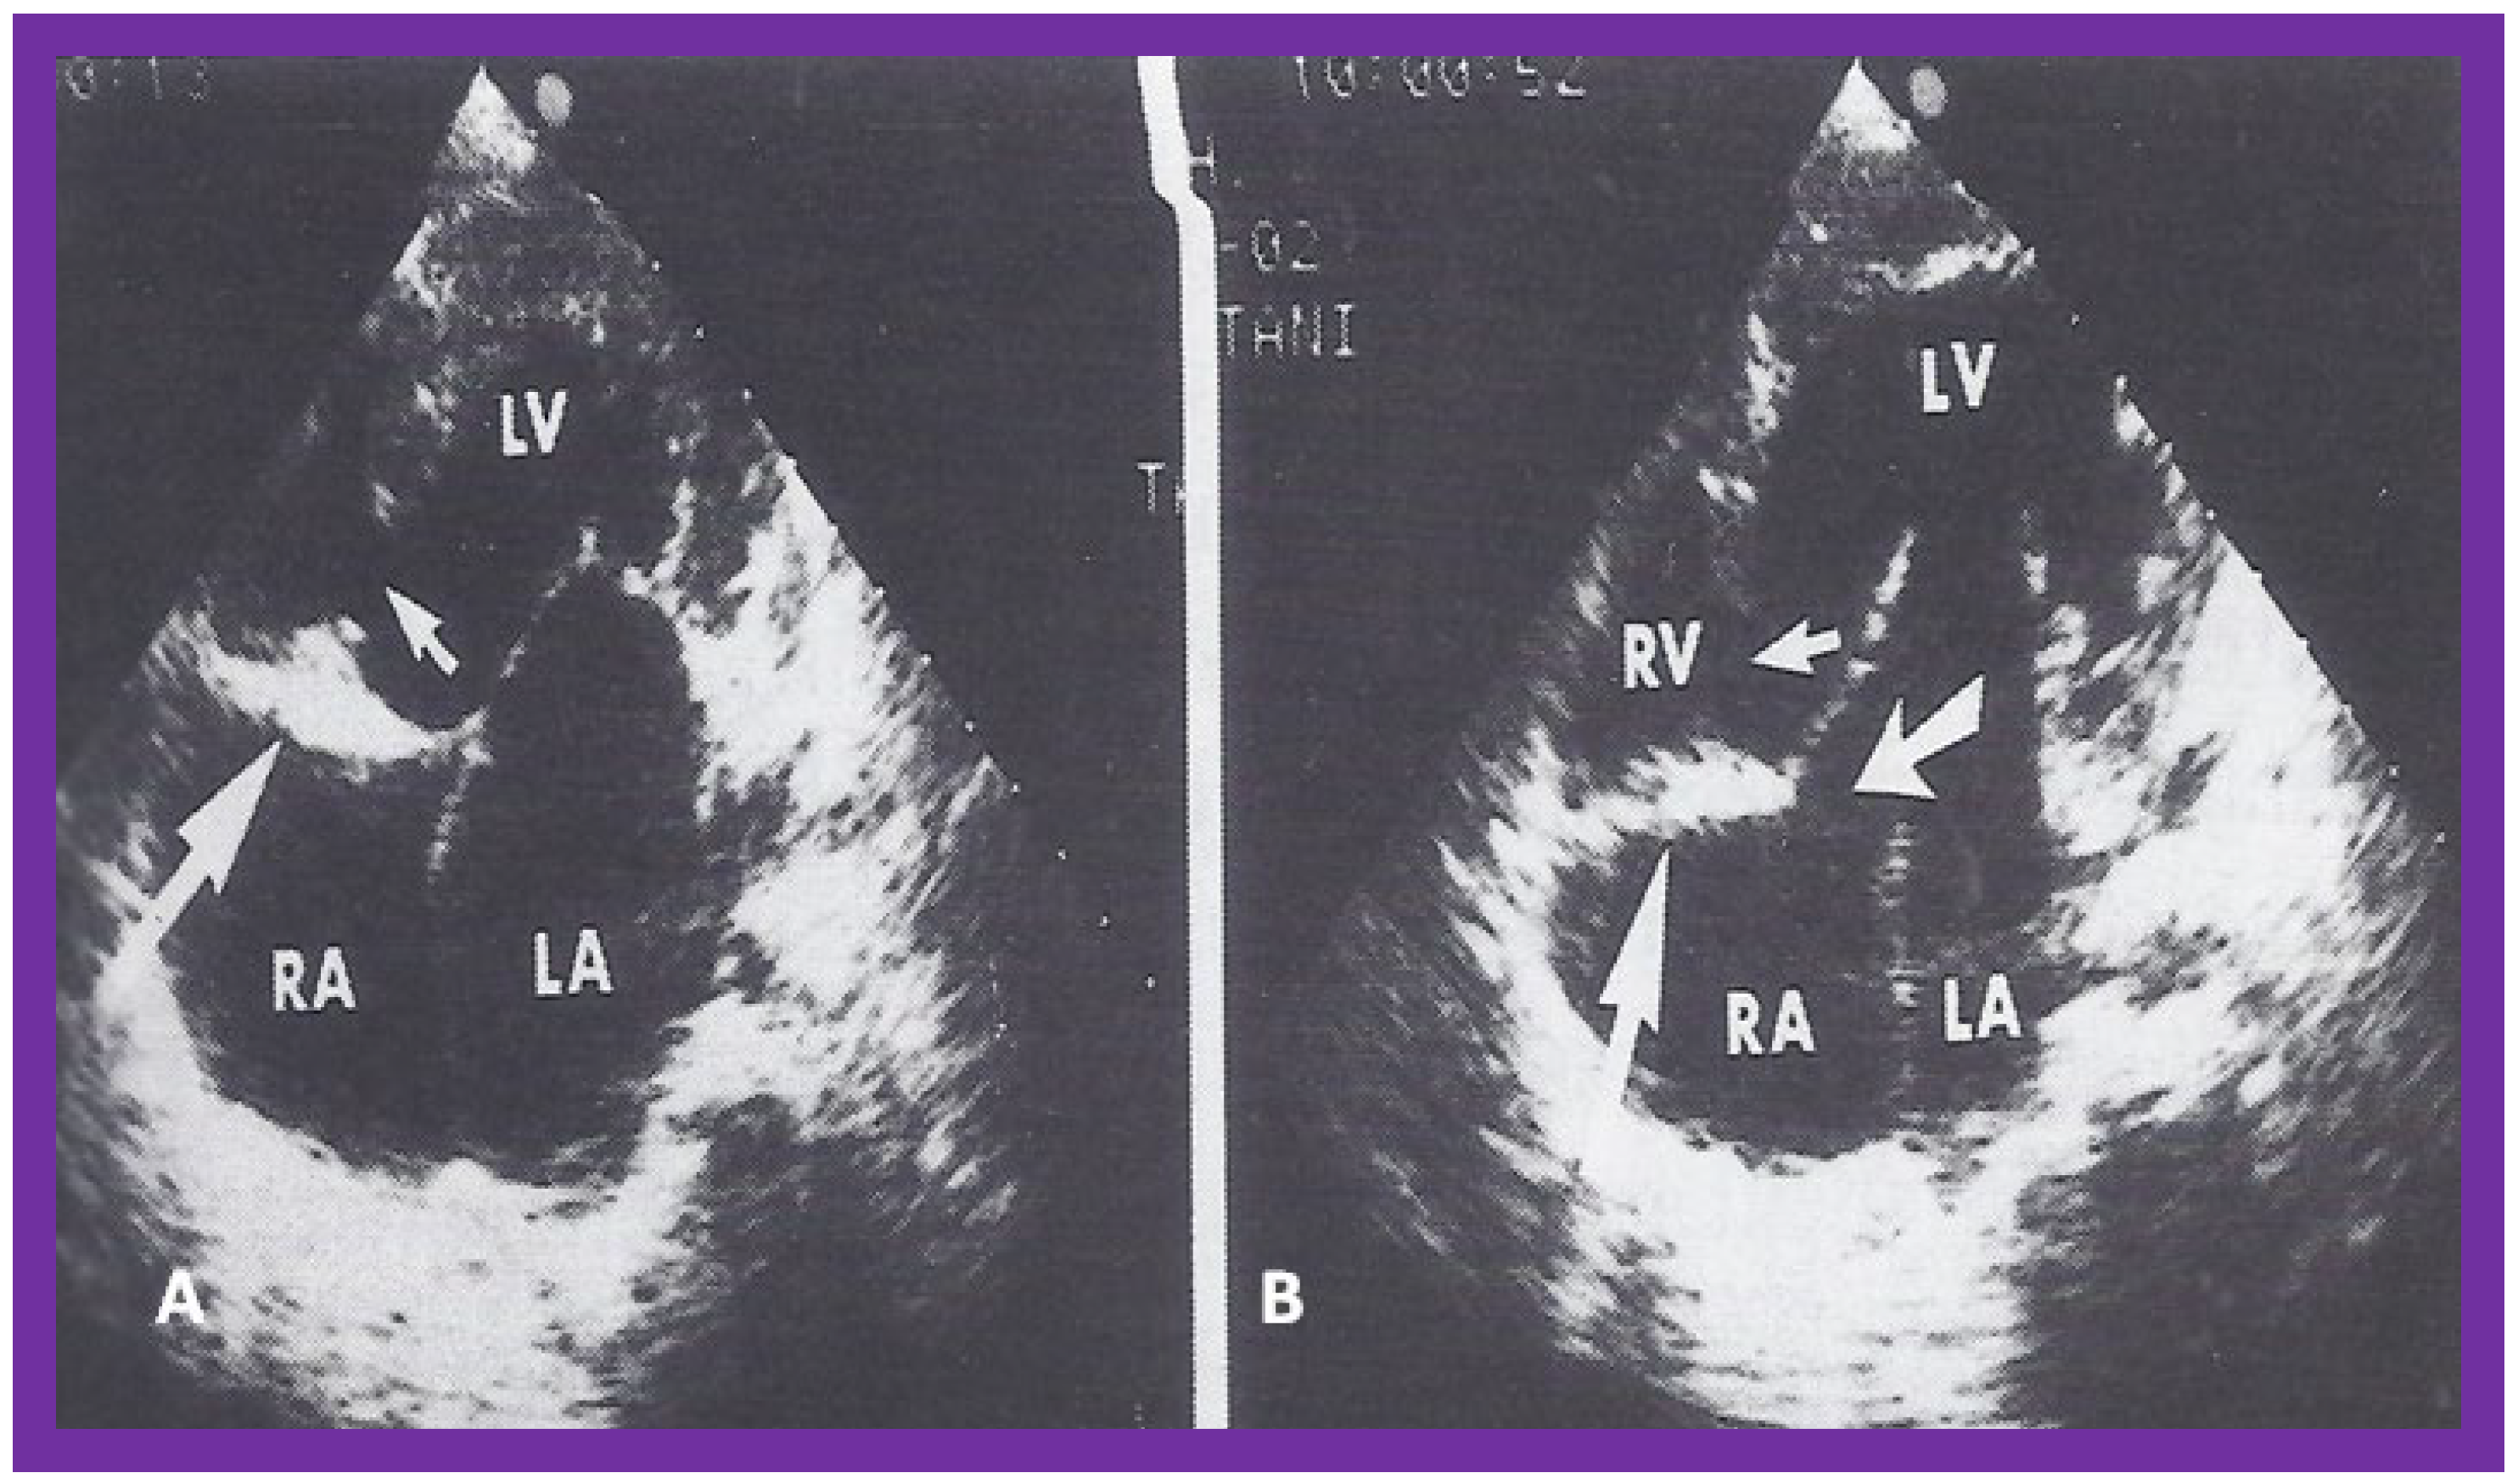

Figure 3. Selected video frames from apical four chamber view of a two dimensional (2D) echocardiographic study, demonstrating a dense band of echoes between the right atrium (RA) and hypoplastic right ventricle (RV). Line drawings are shown beneath the 2D frames. Note that the mitral valve is closed in the left image, while it is open in the right image. The atretic tricuspid valve echoes remain unchanged. LA, left atrium; LV, left ventricle. Reproduced from Reference [24].

At the time of the preparation of the manuscript for the author’s first edition of the book on tricuspid atresia [23], two dimension (2D) echocardiography was being introduced into clinical practice and the 2D pictures were crude, requiring us to juxtapose line drawings [24] to facilitate interpretation of the figures (Figure 3). The published 2D pictures of TA [25,26], prior to ours, were equally crude. These pictures [24,25,26] represented the state of the art echocardiography machines of that time.

Subsequently, improved echocardiography equipment resulted in producing progressively better images [27,28,29] (Figure 4, Figure 5 and Figure 6).